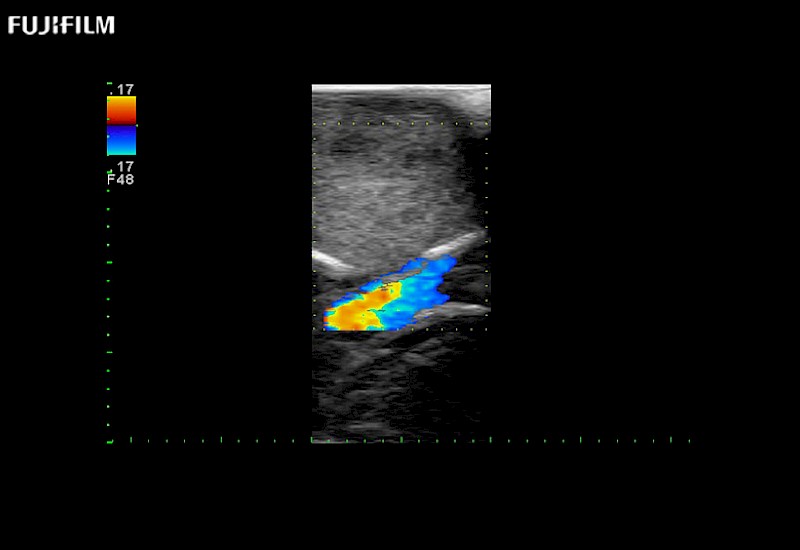

Exclusive 10mm side‐fire linear array transducer with 2.87mm diameter is ideal for real‐time visualization through and behind structures and instant, scalable definition of anatomy and vascularity including the ability to delineate and define tumor margins.

Main Specifications: